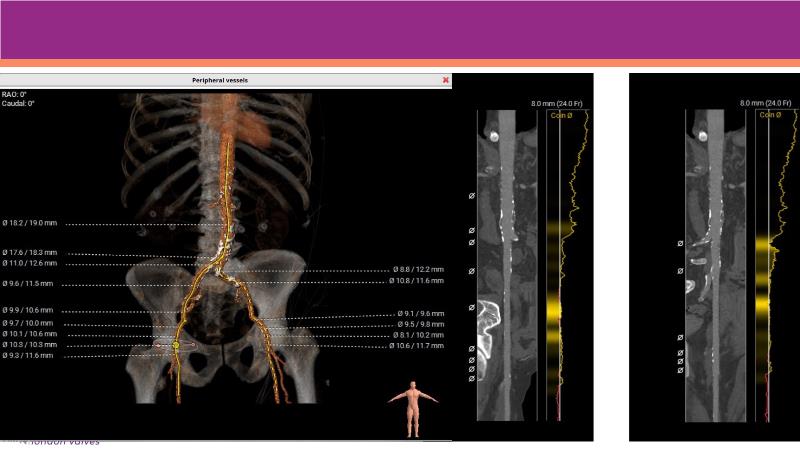

Watch this session to explore expert insights into best-in-class TAVI practices, from pre-procedural imaging and treatment strategy to procedural tips and post-procedural management. Learn from a compelling case study of an 88-year-old male patient with severe symptomatic aortic stenosis treated with the innovative MyVal Octapro THV. Discover key findings from the Landmark RCT sub-group analysis and delve into the unique scientific and design philosophy of MyVal Octapro, along with its real-world clinical potential.

- To learn from the experts best-in-the-class TAVI practice: pre-procedural (Imaging, sizing rationale, treatment strategy), procedural tips and tricks and post-procedural management